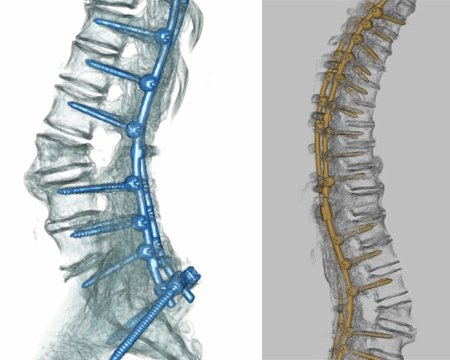

Surgery is performed in both a simultaneous and tandem manner. Each patient’s procedure is tailored to their anatomy and their needs, and different steps of the operation (such as decompression, osteotomies, correction and screw placement) are simultaneously carried out in concert. The surgical team needs to be able to cater to two surgeons performing different steps of the operation at the same time.